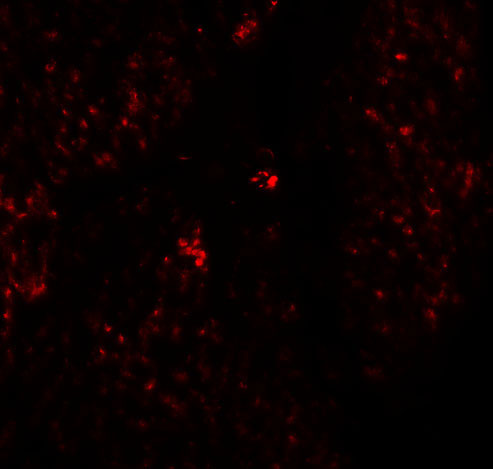

Immunofluorescence of RHAMM in human stomach tissue with RHAM antibody at 20 μg/mL. |